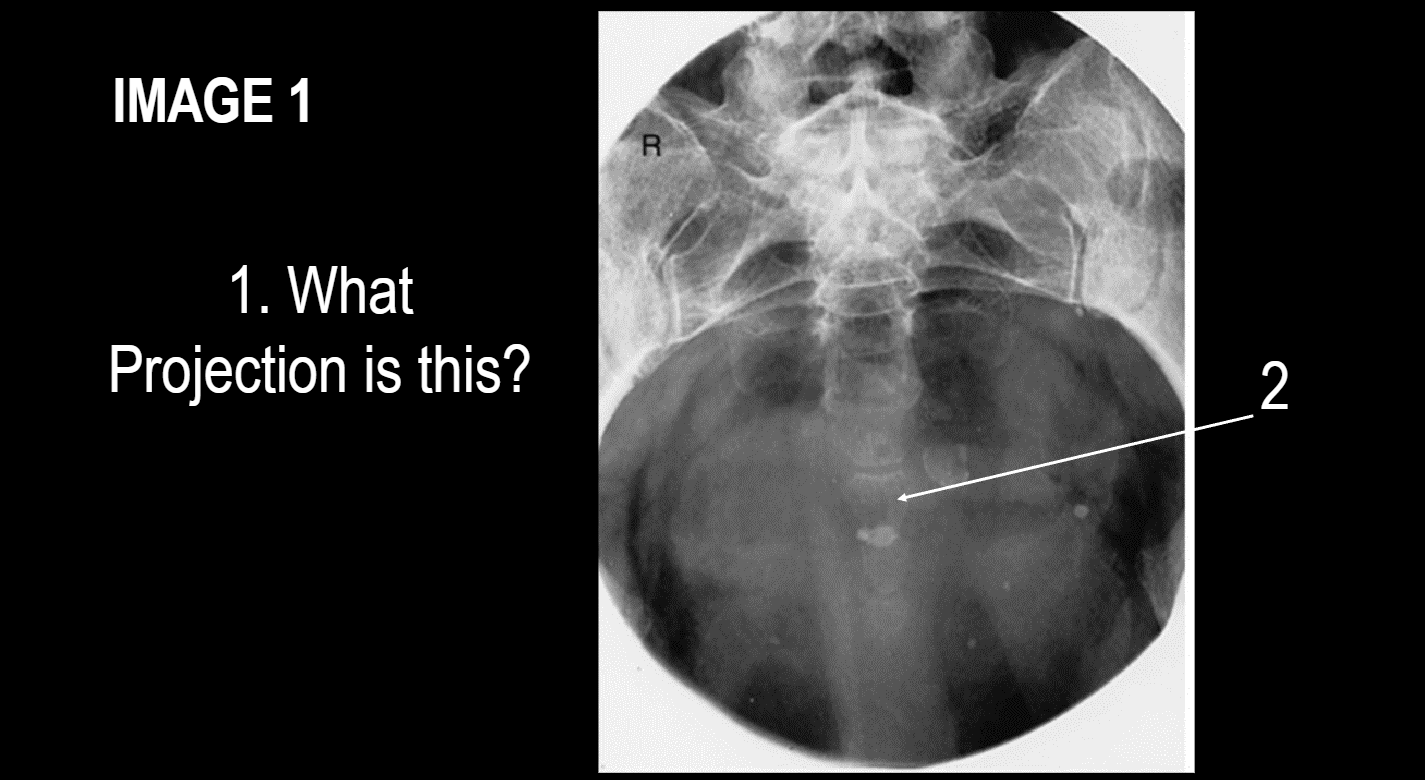

Projection?

AP Axial outlet projection of pelvis, taylor method

This position is used to

image what anatomy?

superior and inferior rami of pubis and ischeal ramus without foreshortening,

AP Axial inlet projection of pelvis, bridgeman method

What anatomy is demonstrated

entire pelvic inlet for trauma assessment